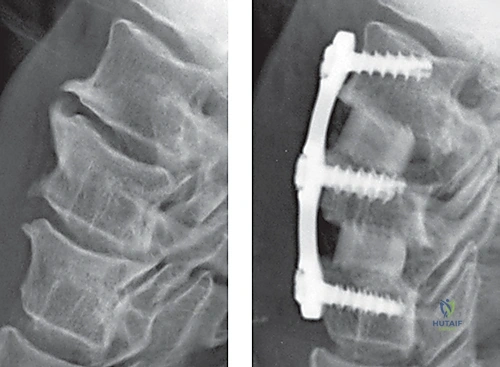

الخطوة 7: التثبيت المعدني (Instrumentation)

لضمان الاستقرار الفوري ومنع حركة الطعم العظمي حتى يكتمل الالتحام (والذي يستغرق أشهراً)، يقوم الدكتور هطيف بتثبيت شريحة معدنية صغيرة من التيتانيوم على الجزء الأمامي من الفقرتين باستخدام براغي دقيقة.